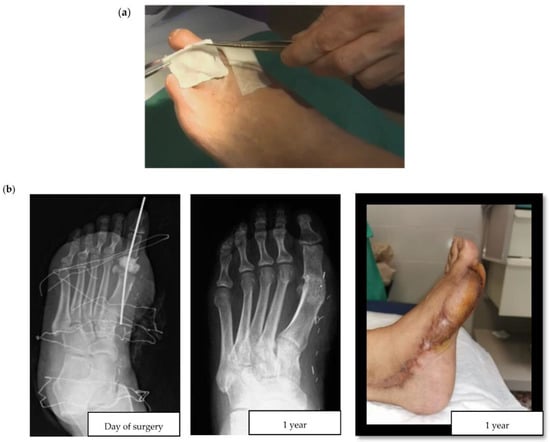

For the purposes of this review, we consistently apply the term topical to refer to the local administration of antibiotics through an infected diabetic foot ulcer (DFU). Topical antibiotic interventions have previously been studied in the assessment of the bioburden and biofilm of diabetic foot wounds [10]. For example, an in vitro experiment compared the efficacy of topical vancomycin and gentamicin to systemic antibiotics for the eradication of polymicrobial biofilms. The authors observed a bioburden reduction of 5 and 8 logarithms (colony forming units per milliliter), a finding with uncertain yet promising clinical relevance, and supportive of further studies to reveal the usefulness of topical antibiotic strategies in the surgical treatment of DFIs [11]. When considering the multiple topical antimicrobials available, it is also worth highlighting that a recent high-quality systematic review failed to show the superiority of any particular topical antimicrobial [12]. This lack of superiority could be partially explained by the local agent choices, encompassing a wide range of antiseptics, antibiotics, and antimicrobial dressings. More consistency in design is seen in clinical studies of local agents in DFIs since the gentamicin collagen sponge and the superficial pexiganan peptide (Figure 1a) tend to be incorporated.

There are two major challenges associated with DFO surgeries: postoperative wound healing in the operated, and ischemia triggered by the residual death space of the former bone. In DFO treatment, two main types of antibiotic delivery system materials are currently available: non-absorbable and absorbable. According to the explored literature, the most frequently used non-absorbable material in DFO is polymethylmethacrylate (PMMA)—an acrylic used extensively in orthopedic surgery for chronic osteomyelitis and implant-related infections [18,19]. Some of the most common antibiotic-loaded commercial PMMA cements include Cemex®, Simplex®, Eurofix®, Palacos®, Copal®, and Refobacin®. As with all non-absorbable materials, the main disadvantage of PMMA is its surgical removal, resulting in additional intervention following the release of all drugs. Alternatively, there are hybrids of biodegradable carrier systems that take advantage of different properties to improve local antibiotic release. They have different presentations, such as Cerament G/V® (see Figure 1b for a clinical case example) or Stimulan® [20]. The development and use of contemporary absorbable biomaterials is an area of ongoing advancement. These materials have some advantages compared to PMMA, including better osteointegration and the lack of need for surgical removal. In this respect, the importance of considering the composition of these materials should also be highlighted, especially as to whether or not they contain hydroxyapatite, which is highly osteoconductive and promotes bone ingrowth. For example, the unique ratio of hydroxyapatite and calcium sulphate in Cerament® makes it particularly suitable for absorption and stimulation of new bone formation at the same rate. In contrast, Stimulan® only contains hemihydrate calcium sulfate, which retains its absorbable properties, but sacrifices osteoconductivity and bone growth.

Figure 1. (a) Application of a collagen sponge on a diabetic foot wound (courtesy of Dr. Ilker Uçkay); (b) Clinical case of a hallux valgus osteomyelitis with bone resection, filling with Cerament G® and a flap. We can observe bone osteointegration 1 year later (courtesy of Dr. Alberto Pérez Fernández).

The authors would like to thank Laia Ferrerons Romero and Sergio Mazuelas Álvarez, members of the Diabetic Foot Unit at Bellvitge Hospital, for kindly providing the pictures and details on the clinical case in Figure 1b.